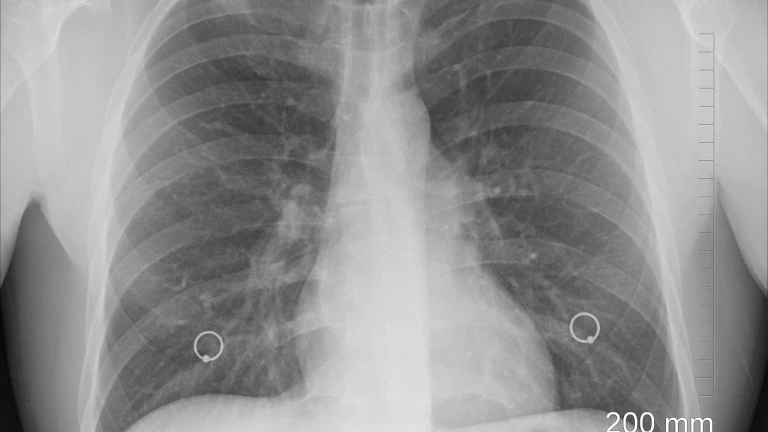

Los hospitales del sistema sanitario público de Andalucía diagnosticaron, en 2021, un total de 4.981 casos nuevos de cáncer de pulmón, lo que supone una prevalencia de 15,21 casos de este tipo de cáncer por 10.000 personas. El cáncer de pulmón es el segundo tumor con mayor incidencia a nivel mundial y el cuarto en España. Sin embargo, es responsable del mayor número de muertes por cáncer en España y a nivel mundial (en torno a un 20% de las muertes por cáncer).

En estas últimas décadas, se ha observado un claro incremento tanto en incidencia como en mortalidad por cáncer de pulmón en mujeres, debido a su incorporación al hábito tabáquico más tardío en las décadas de los 70-80. Actualmente el 25,58% de los diagnósticos de cáncer de pulmón en Andalucía corresponde a mujeres, habiendo aumentado la prevalencia en los últimos ocho años en más de cuatro puntos por cada 10.000 mujeres.

En los últimos años, la incorporación de la inmunoterapia y terapias dirigidas en el algoritmo terapéutico de estos pacientes está permitiendo un importante aumento de la supervivencia y mejora de la calidad de vida de los pacientes andaluces afectados. El mejor conocimiento de las bases moleculares del cáncer de pulmón y los avances terapéuticos y tecnológicos incorporados en su diagnóstico y tratamiento en la última década han convertido a este tipo de tumor en paradigma de la medicina de precisión en Oncología.